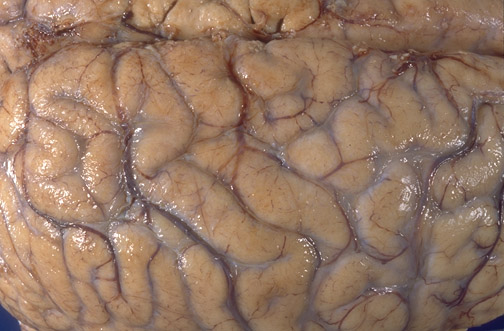

Image 5.1

This is a representation of the gross appearance of the brain that could be present in this patient.